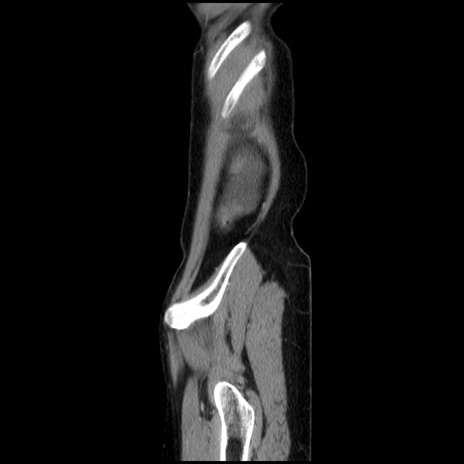

症例32(矢状断像)

【症例】40歳代 女性

【主訴】上腹部痛、嘔気・嘔吐

【現病歴】約9時間前頃から急に上腹部痛、嘔気、嘔吐が出現。改善しないため救急要請。

【既往歴】子宮頚癌(広汎子宮全摘術、放射線療法)、腸閉塞

【身体所見】腹部:平坦、軟、腸雑音亢進、上腹部を中心に腹部全体に圧痛あり。

【データ】WBC 8400、CRP 0.03